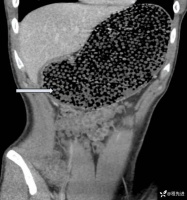

19 岁男子突发腹痛,一看 CT 倒吸一口冷气,密密麻麻